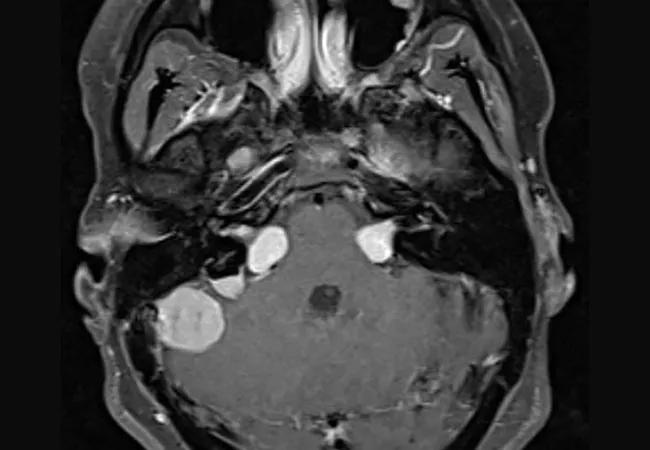

While most meningiomas associated with neurofibromatosis-2 (NF2) grow slowly or not at all within the first years after diagnosis, growth patterns vary markedly, with younger age and the presence of peritumoral brain edema being predictors of growth.

So finds one of the largest single-institution series to date designed to characterize NF2-associated meningiomas and help determine a safe monitoring strategy. The descriptive retrospective study of 137 meningiomas in 48 patients with NF2 identified from Cleveland Clinic electronic medical records was published online in Neurosurgical Focus.

This study is the first series to use volumetric analysis of the entire neuroaxis to assess NF2-associated meningiomas. The authors note that using three-dimensional imaging to monitor tumor growth is important, as linear measurements alone may not reveal volumetric increases and are more subject to reader variation.

The study included 137 meningiomas from 48 patients with NF2 who were seen at Cleveland Clinic between 2000 and 2019. Mean age was 39.5 years at initial imaging, and median follow-up was 32 months (interquartile range: 10.9, 68.3). The average number of tumors per patient was 2.8, with 72.3% of all tumors in female patients. The most common tumor locations were the cerebral convexity (25%), parafalcine region (18%) and spine (10%).

• Peritumoral brain edema was seen at first imaging in 19 tumors (13.9%), and five other tumors (4.2%) subsequently developed it.

• The presence of peritumoral brain edema dramatically increased the risk of growth (odds ratio = 9.12; 95% CI, 1.48-56.4, P = 0.017).